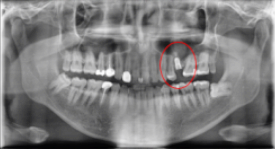

임플란트 1차 치료 후

2021.07.23 / 2021.08.02 (1차,2차 후)

환자분은 상담 1주일 후 내원을 해주셨습니다. 발치와 함께 임플란트 1차 치료가 진행되었습니다.

임플란트 뿌리가 되어줄 '인공치근'을 심었습니다.(1차 치료) 그 후 일주일 뒤 보철과 인근치근을 연결해 주는 지대주를 식립하셨습니다. (2차 치료)

무사히 1차, 2차 치료를 마치셨고, 3개월 뒤 최종 보철물 부착을 위해 내원하시기로 하셨습니다.